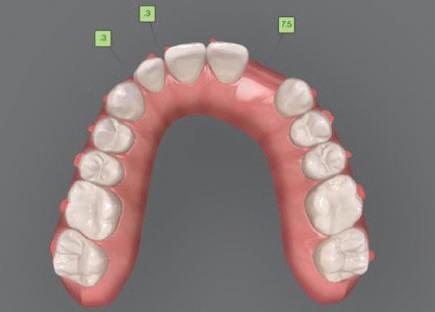

7Dental Tribune Bulgarian Edition / октомври 2022 г. Преди лечението Фиг. 1 Фиг. 4 Фиг. 7 Фиг. 10 Фиг. 13 Фиг. 16 Фиг. 17 Фиг. 18 Фиг. 19 Фиг. 20 Фиг. 11 Фиг. 14 Фиг. 12 Фиг. 15 Фиг. 8 Фиг. 9 Фиг. 5 Фиг. 6 Фиг. 2 Фиг. 3

Dental Tribune Bulgarian Edition / октомври 2022 г.16 клиничен случай с алайнери Г орният латерален ре зец е вторият найчесто вродено липсващ зъб.1,2 Поради разполо жението му във видимата зона на усмивката лечение то на подобни случаи нала га мултидисциплинарен под ход, целящ отличен функцио нален и естетичен резултат. Налице са няколко лечебни мо далности, свързани с различ но разпределение на място то: първият вариант е орто донтско отваряне на място и възстановяване на липсва щия зъб с конструкция, под държана от съседните зъби3 или от имплант4, докато при втория подход разстоянията се затварят и премоларът заема мястото на канина.5 Изборът на лечебен подход трябва да бъде направен съв местно от зъболекар и паци ент въз основа на очакванията на последния и предвиди мостта на лечението. Множе ство фактори влияят върху това решение, като напри мер типа малоклузия, размера, формата и цвета на кучеш ките зъби6, оклузалните вза имоотношения (овърджет и овърбайт), лицевия профил, дължината на зъбната дъга и несъответствията в разме ра на зъбите.7 В настоящата публикация се разглежда случаят на жена в зряла възраст с вродена лип са на горен ляв латерален резец. Бяха приложени про зрачни алайнери за отваряне на място за единичен им плант и бяха постигна ти функционална оклузия и отлична естетика. ПРЕДСТАВЯНЕ НА СЛУЧАЯ Диагноза Пациентката бе на 32 годи ни, когато лечението започна, и първоначалното ѝ състоя ние бе следното (фиг. 1–3): липсващ горен ляв латерален резец; клас II, подклас I малоклузия; отклонение на горната сре динна линия вляво; Доклад на клиничен случай ЛЕЧЕНИЕ С АЛАЙНЕРИ НА ПАЦИЕНТ С АГЕНЕЗИЯ НА ЛАТЕРАЛЕН РЕЗЕЦ Д-р Iro Eleftheriadi и д-р Christodoulos Laspos, Гърция и Кипър Фиг. 1a–h Предоперативни лицеви и интраорални снимки. Фиг. 2a–e Дигитални модели преди началото на лечението. Фиг. 3 Панорамна снимка преди лечението. Фиг. 1a Фиг. 1d Фиг. 1f Фиг. 2a Фиг. 2d Фиг. 2b Фиг. 2e Фиг. 3 Фиг. 2c Фиг. 1b Фиг. 1e Фиг. 1g Фиг. 1h Фиг. 1c